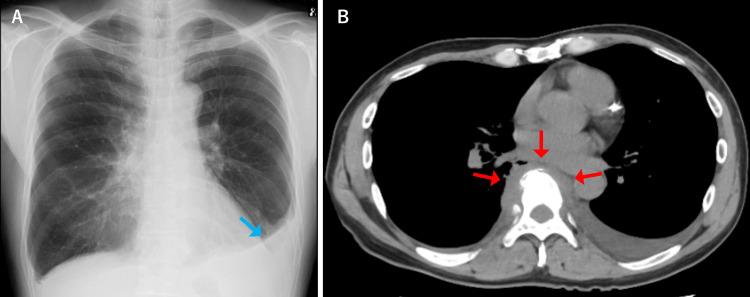

Pyogenic spondylitis typically presents with back and neck pain, fever, and fatigue. Sharp chest pain upon deep breathing, commonly associated with pleurisy, is not a typical manifestation of pyogenic spondylitis. We report a case of pleuritic chest pain as the initial presentation of pyogenic spondylitis. A 62-year-old male patient presented with a one-week history of right-sided pleuritic chest pain and fever. Chest computed tomography (CT) revealed a right pleural effusion. The patient was initially treated for bacterial pleurisy without improvement and subsequently developed back pain. Blood cultures yielded methicillin-resistant ( ​​​​). Additional thoracic spine magnetic resonance imaging (MRI) demonstrated pyogenic spondylitis with abscess formation on the right side of the vertebral body. The final diagnosis was pyogenic spondylitis that had progressed and spread inflammation to the pleura. This case highlights that pyogenic spondylitis can cause secondary pleurisy due to extension of inflammation to adjacent structures, a possibility that should be recognized. When  bacteremia is detected during the course of pleurisy, clinicians should consider secondary pleurisy and perform imaging studies to evaluate for pyogenic spondylitis.

化脓性脊柱炎通常表现为背部和颈部疼痛、发热及乏力。深呼吸时出现的尖锐胸痛,通常与胸膜炎相关,并非化脓性脊柱炎的典型表现。我们报告一例以胸膜炎性胸痛为首发表现的化脓性脊柱炎病例。一名62岁男性患者,有一周右侧胸膜炎性胸痛及发热病史。胸部计算机断层扫描(CT)显示右侧胸腔积液。该患者最初按细菌性胸膜炎治疗但无改善,随后出现背痛。血培养检出耐甲氧西林(此处原文缺失内容)。额外的胸椎磁共振成像(MRI)显示化脓性脊柱炎,椎体右侧有脓肿形成。最终诊断为化脓性脊柱炎,炎症进展并蔓延至胸膜。该病例强调化脓性脊柱炎可因炎症蔓延至相邻结构而导致继发性胸膜炎,这一可能性应得到认识。当在胸膜炎病程中检测到菌血症时,临床医生应考虑继发性胸膜炎并进行影像学检查以评估是否存在化脓性脊柱炎。